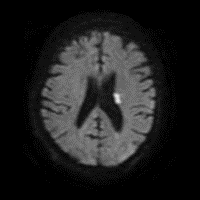

5/ Because the lesion is calcified and suspected to represent ruptured plaque, they are loaded with ASA/Plavix and admitted for close monitoring. MRI shows small infarct: